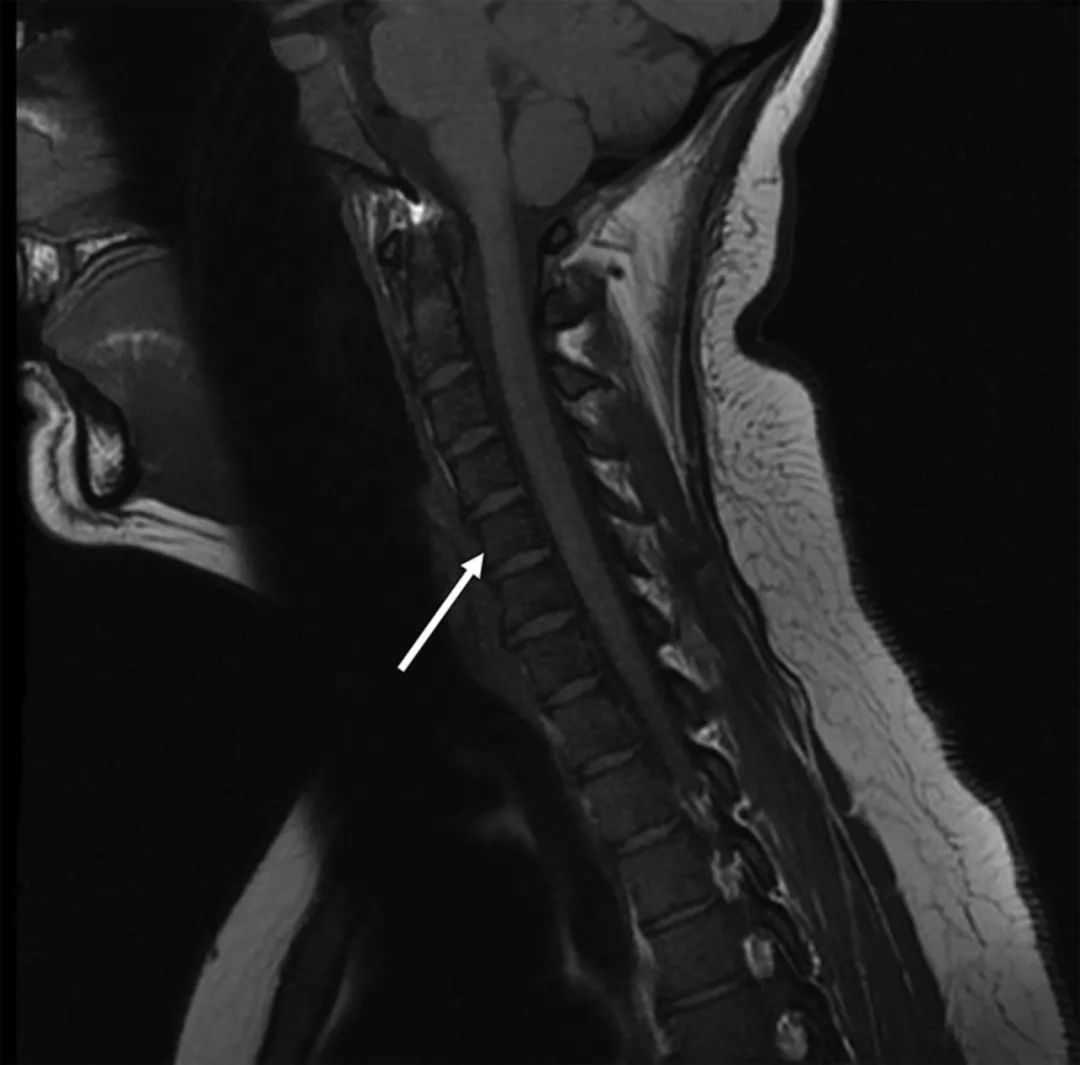

根据最新美国妇科学会指南,怀孕期间应避免使用钆增强[4],因此患者进行了头颅和颈椎的MRI平扫,结果未见脑或脊髓存在明显异常,但由于未进行增强,脑膜病变不能很好显示。但椎骨骨髓存在异常且伴有弥漫性T1低信号(图2)。结合患者临床表现,该影像表现提示肿瘤骨髓浸润。

图2 患者颈椎MRI检查结果。T1矢状位影像显示骨髓弥漫性低信号(箭头),符合急性白血病细胞浸润。